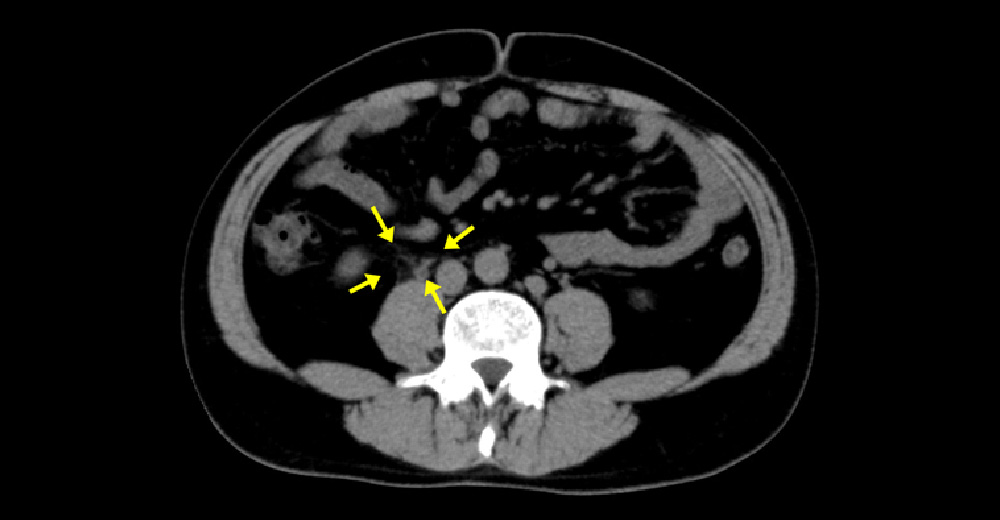

尿管結石

激しい背部痛や腹痛を主訴として受診された症例です。エコーでも見逃されやすく、確定診断にはCTが有用です。

右尿管が軽度拡張し、周囲に炎症を思わせる脂肪織混濁を認めます。

白い粒が右尿管内の結石です。